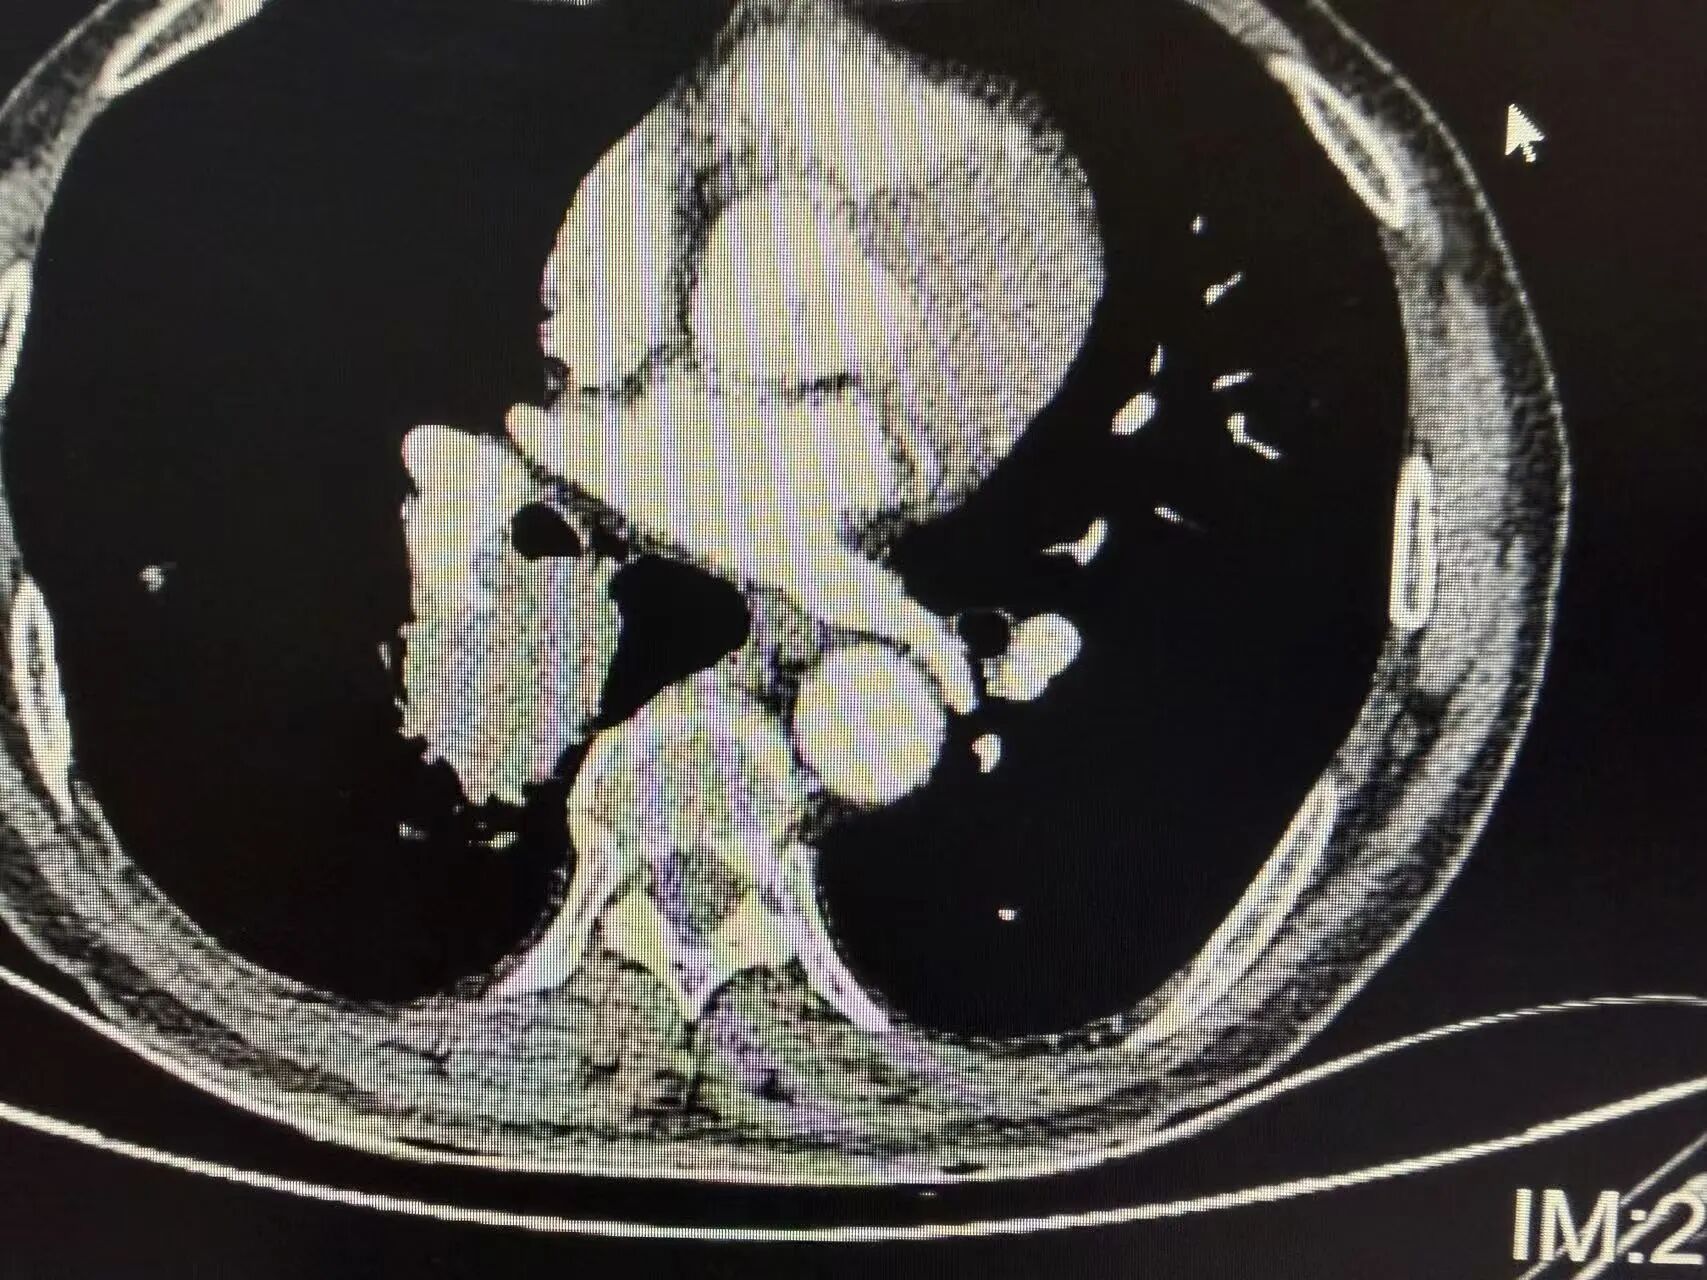

胸部CT:提示右下肺占位,病灶位置靠近肺门,已侵犯肺动脉,直接手术难度大、风险高。

治疗前胸片可见右肺门区域明显占位阴影,肿瘤体积较大,位置深、靠近中心大血管